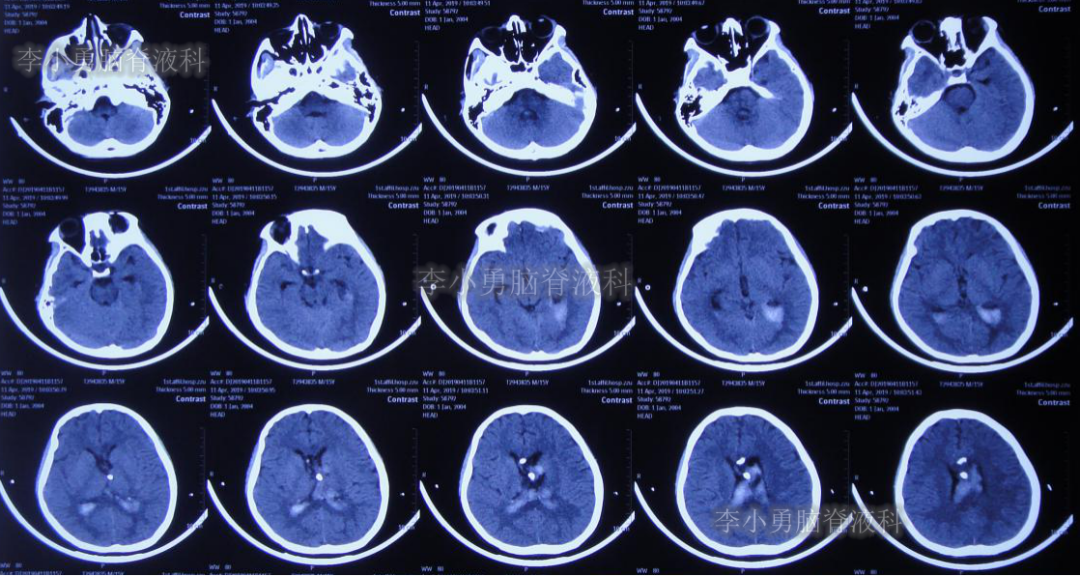

2019年3月26日患者突发头痛及呕吐,随后出现晕厥。急救车送至河南省周口市某医院。行头颅CT(图-1):脑室内出血,次日急诊给予行双侧脑室外引流术(图-2)(第一次的脑室外引流术)。

图-1:2019年3月26日头颅CT:脑室内出血

图-2:2019年3月27日头颅CT:双侧脑室外引流术后